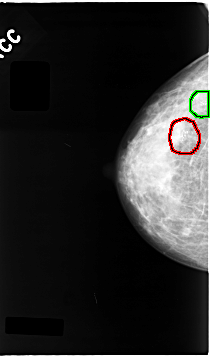

FILE: C_0063_1.RIGHT_CC.OVERLAY

TOTAL_ABNORMALITIES 2

ABNORMALITY 1

LESION_TYPE CALCIFICATION TYPE PLEOMORPHIC DISTRIBUTION CLUSTERED

ASSESSMENT 5

SUBTLETY 5

PATHOLOGY MALIGNANT

TOTAL_OUTLINES 1

BOUNDARY

ABNORMALITY 2